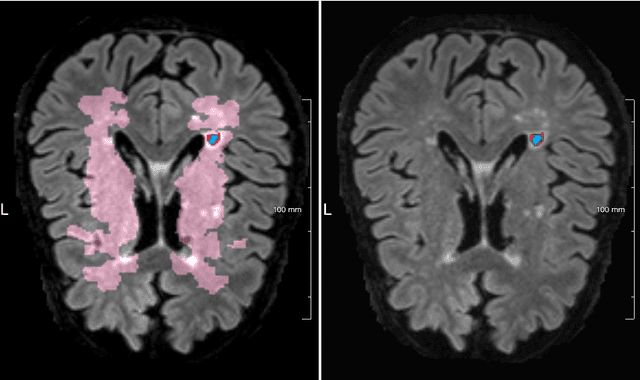

Abstract:Imaging markers of cerebral small vessel disease provide valuable information on brain health, but their manual assessment is time-consuming and hampered by substantial intra- and interrater variability. Automated rating may benefit biomedical research, as well as clinical assessment, but diagnostic reliability of existing algorithms is unknown. Here, we present the results of the \textit{VAscular Lesions DetectiOn and Segmentation} (\textit{Where is VALDO?}) challenge that was run as a satellite event at the international conference on Medical Image Computing and Computer Aided Intervention (MICCAI) 2021. This challenge aimed to promote the development of methods for automated detection and segmentation of small and sparse imaging markers of cerebral small vessel disease, namely enlarged perivascular spaces (EPVS) (Task 1), cerebral microbleeds (Task 2) and lacunes of presumed vascular origin (Task 3) while leveraging weak and noisy labels. Overall, 12 teams participated in the challenge proposing solutions for one or more tasks (4 for Task 1 - EPVS, 9 for Task 2 - Microbleeds and 6 for Task 3 - Lacunes). Multi-cohort data was used in both training and evaluation. Results showed a large variability in performance both across teams and across tasks, with promising results notably for Task 1 - EPVS and Task 2 - Microbleeds and not practically useful results yet for Task 3 - Lacunes. It also highlighted the performance inconsistency across cases that may deter use at an individual level, while still proving useful at a population level.

Abstract:Cerebral microbleeds are small, dark, round lesions that can be visualised on T2*-weighted MRI or other sequences sensitive to susceptibility effects. In this work, we propose a multi-stage approach to both microbleed detection and segmentation. First, possible microbleed locations are detected with a Mask R-CNN technique. Second, at each possible microbleed location, a simple U-Net performs the final segmentation. This work used the 72 subjects as training data provided by the "Where is VALDO?" challenge of MICCAI 2021.